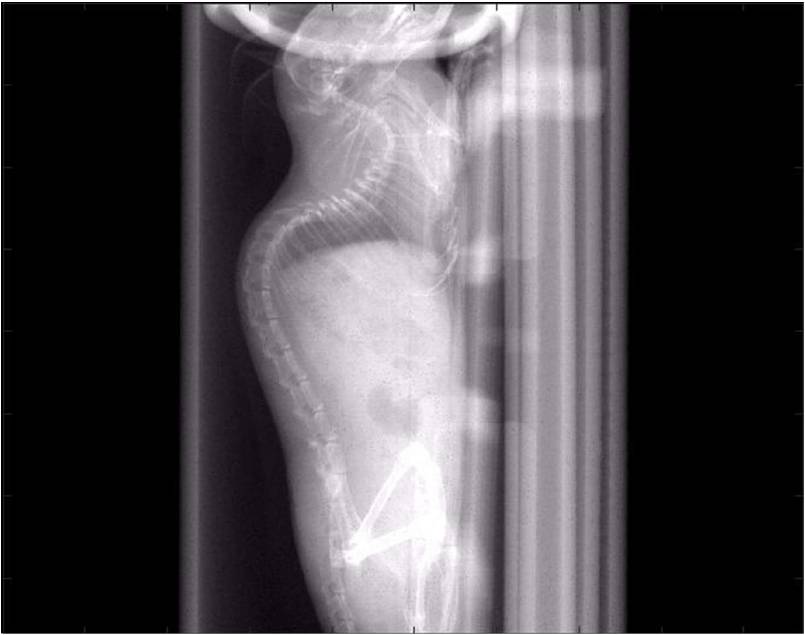

檢測案例

小鼠股骨

超高分辨率模式下像素大小為9μm。

A軸向和矢狀面顯示小鼠股骨結構。

B用鈦材料植入的穿過骨頭的冠狀切片